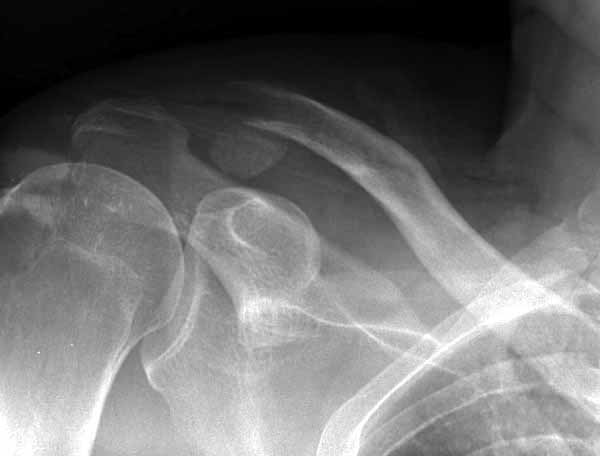

1.JPG

60KB (62415 bytes)

|